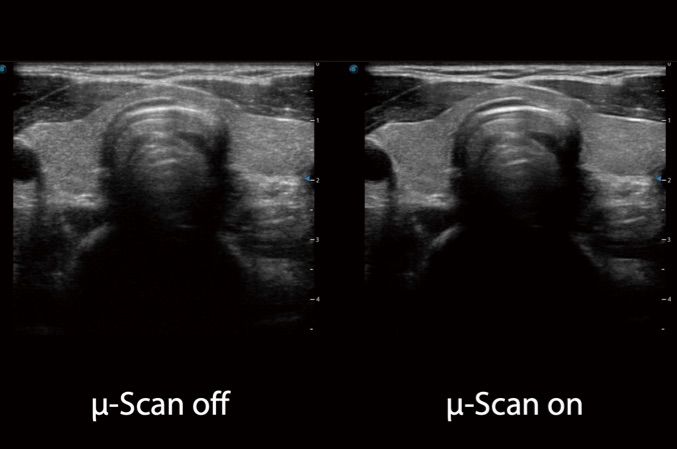

微米成像技術(shù)大大提高了器官和病變的可見性。高清對比度分辨率將抑制斑點(diǎn)噪聲,同時(shí)保持真實(shí)的組織結(jié)構(gòu)。